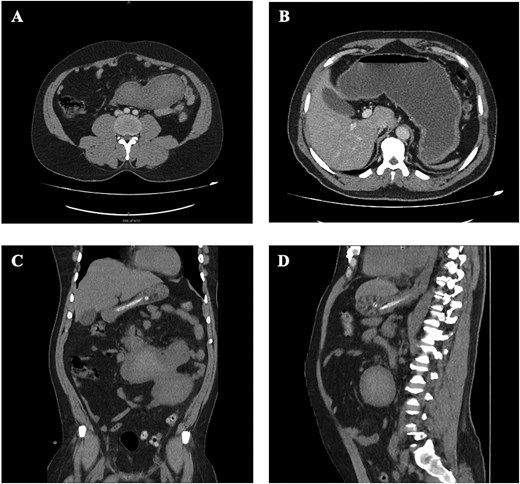

A contrast-enhanced computed tomography (CT) scan of the abdomen revealed a large, lobulated mass measuring 7.5 cm in the anterior–posterior dimension, 15 cm in the transverse dimension, and 16 cm in the craniocaudal dimension. The mass exhibited areas of mixed high attenuation, suggestive of hemorrhagic content. It was found to be communicating with soft tissue thickening in the third part of the duodenum, which was inseparable from the head of the pancreas. Accompanied by surrounding inflammation, mild free fluid, and resultant upstream fluid-filled dilation of the stomach, pylorus, and proximal duodenum, indicating an upper gastrointestinal obstruction (Fig. 1). Additionally, there was a hiatal hernia containing part of the gastric fundus, which showed wall thickening and surrounding free fluid, raising concerns for early congestion. Esophagogastroduodenoscopy (EGD) demonstrated severe esophagitis and cardia incompetence with a 3-cm hiatus hernia.

CT finding. (A, B) CT scan of abdomen, axial view. Showing an intra-abdominal large, lobulated mass, with internal mixed high attenuation, suggestive of hemorrhagic content. With resultant dilatation of the stomach and proximal duodenum. (C) CT scan of abdomen, coronal view. (D) CT scan of abdomen, sagittal view.